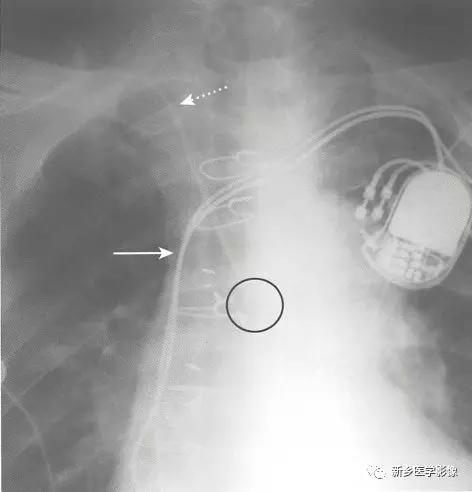

●CVC为无标志条的均匀不透光的细导管(直径约3mm )。

●通常通过锁骨下静脉或颈内静脉插入。颈内静脉汇入锁骨下静脉形成头臂静脉(无名静脉),再汇入上腔静脉。锁骨下静脉和头臂静脉的交汇处通常位于锁骨内侧端后方。

●CVC下行前应到达锁骨内侧端,CVC管头应位于第一肋前端内侧。

●导管应沿胸椎右缘向下走行,管头应位于上腔静脉内。

●CVC导管的弯曲都应是平滑的,而不是锐利弯折。

●漂浮导管与中心静脉导管外形相似,但长一些。

●通过锁骨下静脉或颈内静脉插入,管头漂浮进入右或左肺动脉的近端。漂浮导管的管头距肺门不应超过2cm。

●双腔导管是典型的具有中心标志条的较大孔径导管。

●不同品牌的设计略有不同,但每根导管都有2个同轴的腔,目的都是使两出口间的再循环量最小。“动脉端”(血液由此离开体内)较“静脉端”(血液由此回到体内)为近端,这样可减少再循环血量。

●一些导管设计为2个分离的腔,其中一个管头位于,上腔静脉内,另一个管头位于右心房内。

●经右侧颈内静脉路径是最常使用的路径:临时使用(2~3周)的导管管头通常位于,上腔静脉内,较长期的导管管头多位于右心房内。